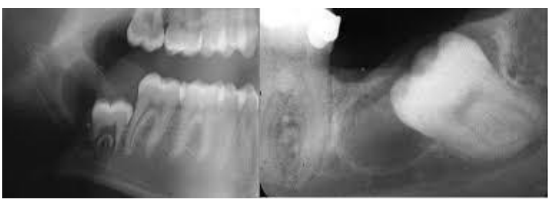

No aspecto clínico-radiográfico, o cisto dentígero costuma apresentar-se como uma imagem radiolúcida unilocular bem definida (Figura 1), geralmente localizada na região posterior da mandíbula, com maior frequência de envolvimento do elemento 38 (Terauchi et al., 2019). A tomografia computadorizada de feixe cônico tem sido considerada o exame mais preciso para avaliação da relação da lesão com estruturas adjacentes (Yalçin et al., 2022). A depender da sua evolução, pode provocar deslocamento dentário, reabsorção radicular e até mesmo quadros dolorosos e infecções, o que justifica a importância de uma abordagem terapêutica adequada (Aoki et al., 2022).

Figura 1 – Áreas radiolúcida unilocular sugestiva de um cisto dentígero associadas a terceiros molares